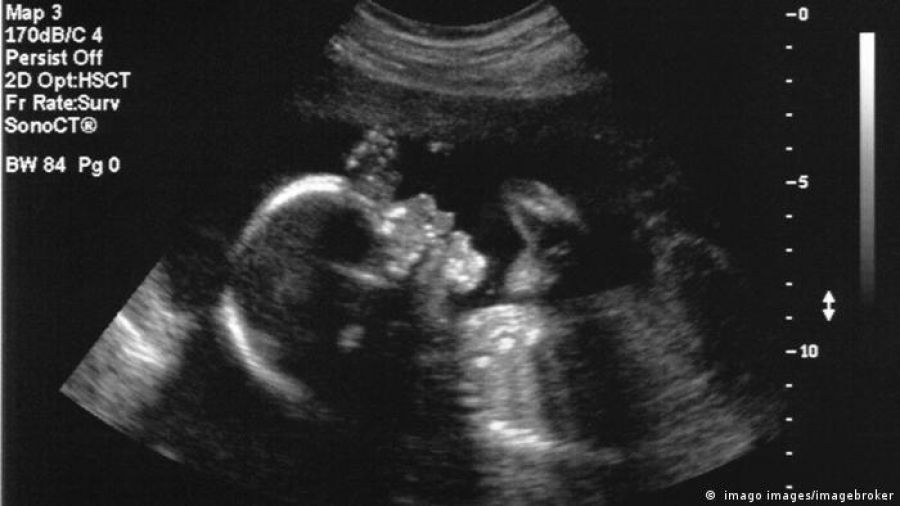

La técnica quirúrgica, llevada a cabo con una ecografía y con el feto aún en el interior del útero, podría ayudar a tratar una rara afección prenatal antes de que aumente el riesgo de complicaciones tras el nacimiento.

En una primicia mundial, unos médicos cirujanos han logrado operar exitosamente una malformación del cerebro de un feto de 34 semanas y 2 días de gestación, mientras este todavía se encontraba en el útero, según se describe en un estudio publicado este jueves (04.05.2023) por la revista Stroke.

Con la ayuda de una ecografía, los doctores utilizaron una técnica quirúrgica llamada embolización para tratar una malformación de la vena de Galeno, una rara afección prenatal que afecta al cerebro y que suele tratarse después del nacimiento.